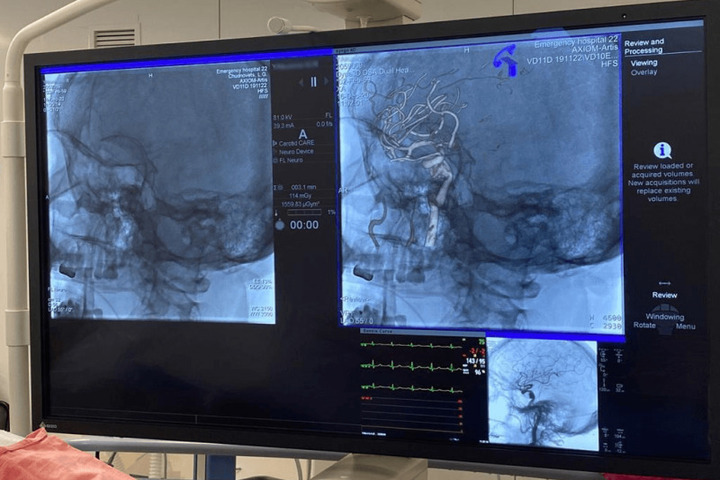

В столице Башкирии врачи больницы скорой медицинской помощи провели уникальную операцию, установив потоковый плетеный стент особой конструкции в артерию на уровне аневризмы в голове пациента.

Процедуру провели с помощью нового ангиографа, который в больницу поставили в рамках нацпроекта «Здравоохранение».